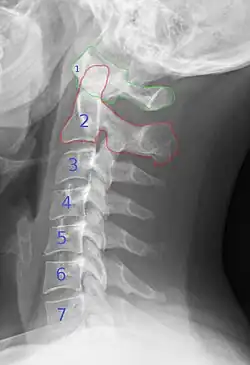

Röntgenbild der Halswirbelsäule im seitlichen Strahlengang. Die Wirbel sind mit Nummern markiert. Der Atlas (1) und der Axis (2) sind farbig umrandet.

Beim Menschen liegt direkt unter dem Foramen magnum des Schädels der erste Halswirbel, der Atlas. Dieser ist nach Atlas aus der griechischen Mythologie benannt. Der Atlas trägt den Schädel und umfasst dabei den Zahn des zweiten Halswirbels, des Drehers (lat. Axis). Die Gelenke zwischen Schädelbasis und Axis bilden zusammen zwei Kopfgelenke, welche etwa 70 % der Beweglichkeit des Kopfes im Verhältnis zum Rumpf gewährleisten.

Die weiteren Halswirbel haben die übliche Form eines Wirbels mit dem Wirbelkörper und dem das Rückenmark umfassenden Wirbelbogen, an dessen seitlichen Fortsätzen sich jeweils rechts und links des Wirbelkanals die Wirbelbogengelenke oder auch Facettengelenke befinden.

Der 7. Halswirbel der menschlichen Wirbelsäule wird als Vertebra prominens (vorstehender Wirbel) bezeichnet, weil sein Dornfortsatz etwas weiter nach hinten vorsteht als der der anderen sechs Halswirbel. Daher ist der Dornfortsatz des 7. Halswirbels von außen am unteren Ende der Nackenfurche meist gut zu tasten und dient als anatomischer Orientierungspunkt.